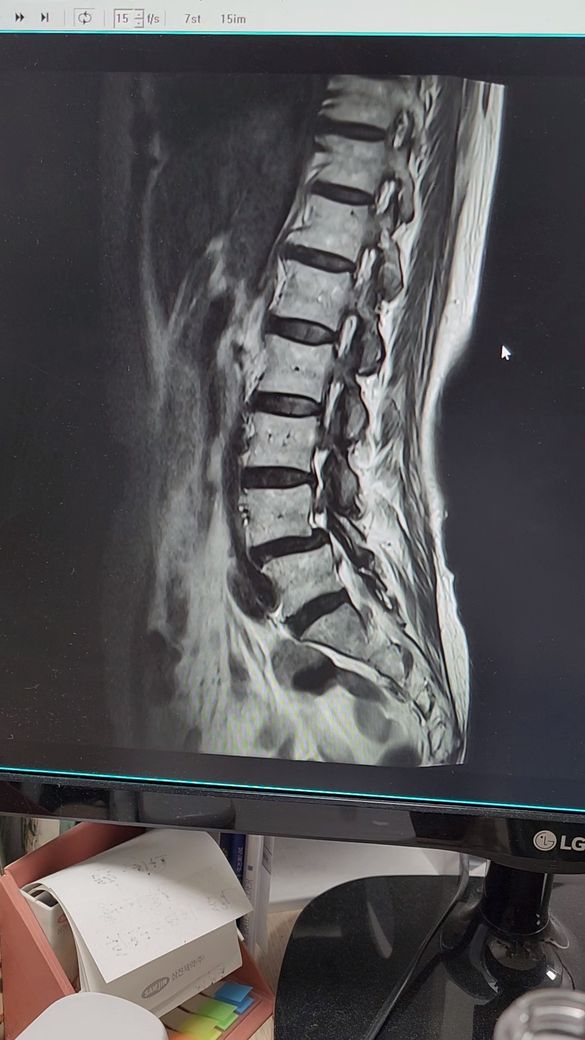

허리디스크 추간판탈출증.전방전위증

4월5일 척추,4.5번

추간판탈출증과 전방전위증으로 왼쪽 엉치부분과 사타구니 허벅지 뒷쪽 방사통과 다리저림이 심해요.처음엔 걷지도 못하고 한달반정도 물리치료,도수치료.약물치료하다가 좋아지질않아서

최근에는 디스크, 즉 추간판탈출증은 비수술적 치료를 유지하는 것이 유행이지만

반복적인 시술에도 호전이 없고 통증이 지속되는 경우에는 수술을 고민하는 것이 더

효과적일 수 있습니다. 수술 후에도 재발은 가능하지만 수술 후 재활과 관리를 통해

이전보다 통증이 덜할 수 있는 것이 사실입니다.